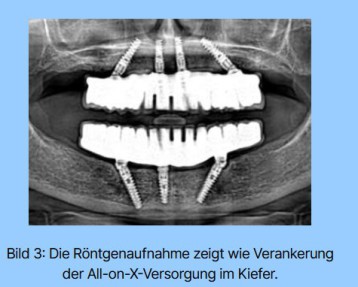

Anbei sehen Sie ein Beispiel aus meiner Praxis mit einer Versorgung von 3 Implantaten im Unterkiefer.

All-on-3 ist ein modernes Behandlungsprotokoll zur Vollversorgung des zahnlosen Unterkiefers auf nur drei Implantaten.

Die drei Implantate werden operativ in optimaler Position eingesetzt und tragen gemeinsam eine stabile, ästhetisch anspruchsvolle Brücke.